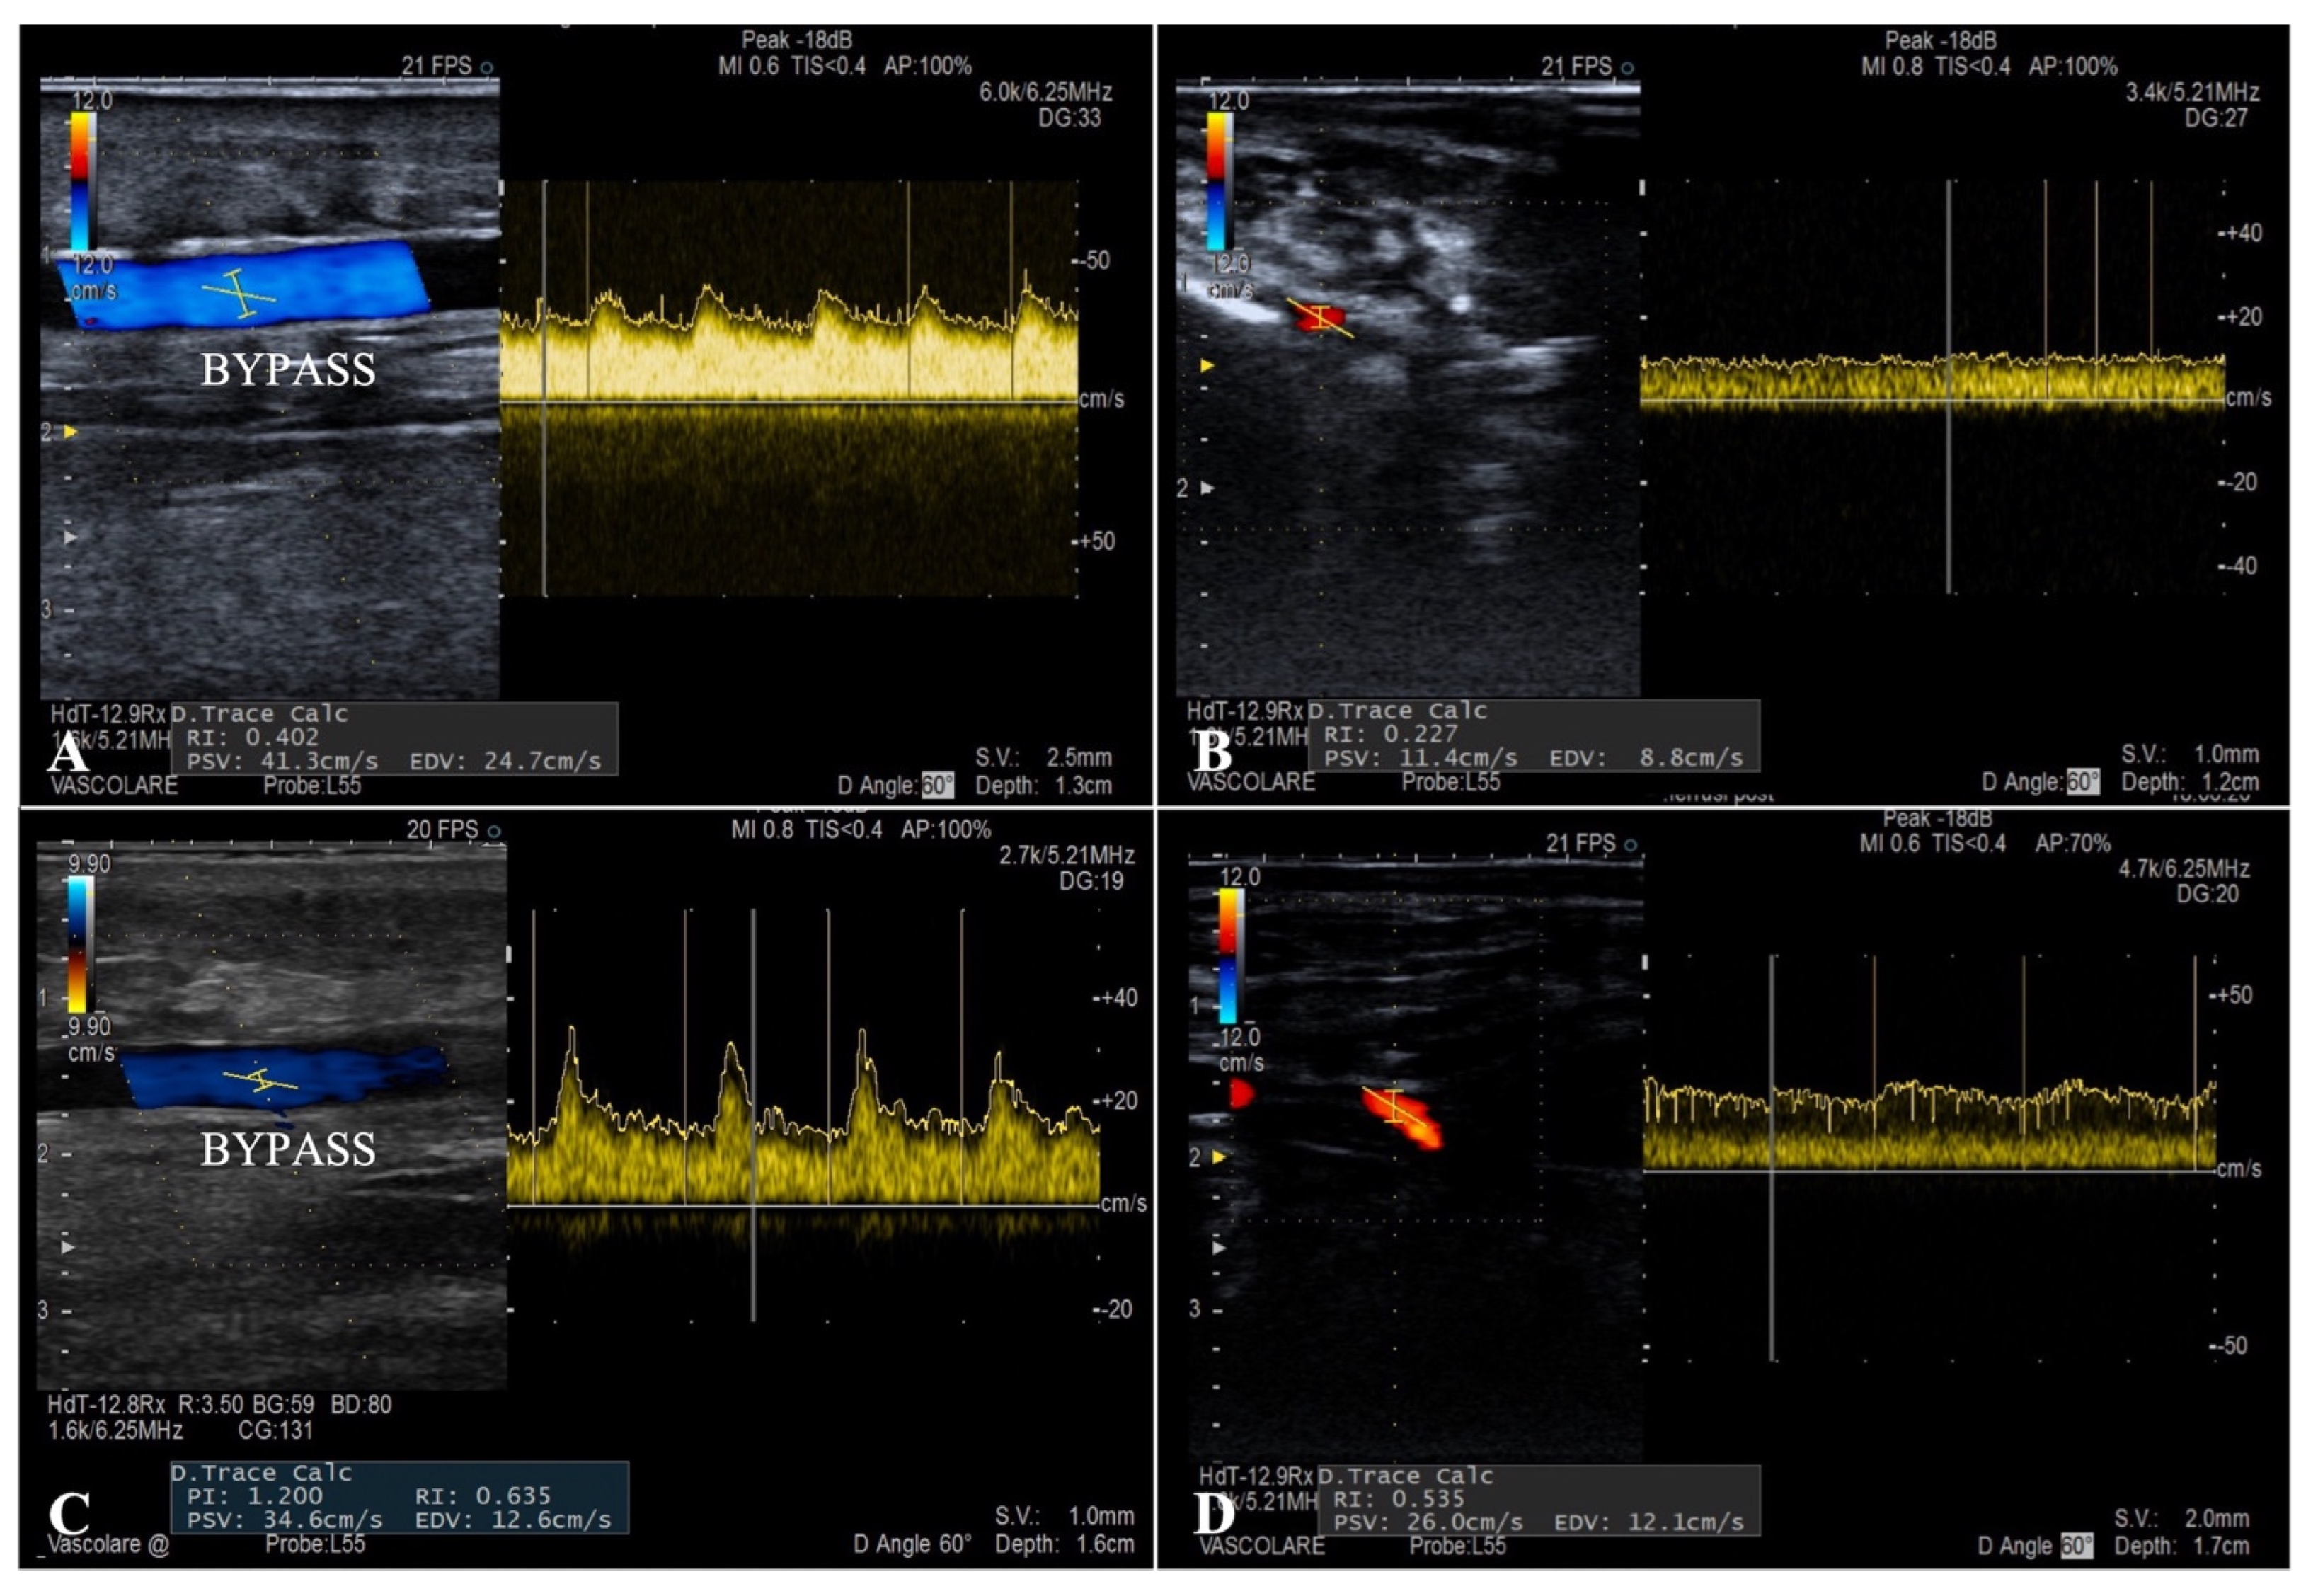

The flow curves analysis performed during the ultrasound follow-up showed a systolic peak never exceeding 130 cm/s (mean PSV 76 cm/s) and a well-represented diastolic curve in all the patients (mean EDV 45 cm/s), typical characteristics of parenchymal destination flows (

Figure 4). Duplex examination revealed a considerable increase in the mean RI after the endovascular embolization inside the bypass and at the level of the distal foot arteries (0.52 and 0.62 vs. 0.36 and 0.41, respectively).

To guide the correct timing of the secondary procedure, duplex ultrasound examination was performed with an accurate analysis of the flow curves. Peak systolic velocity, showing a systolic peak never exceeding 130 cm/s and a well-represented diastolic curve in all patients was visible, and these are typical characteristics of parenchymal destination flows. The mean value of post-embolization RI was 0.62, indicating how the arterialization of the deep venous system allows a retrograde perfusion of the microcirculation in a territory with terminal vascularization.